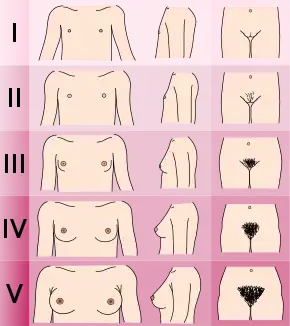

Puberty is considered delayed when the child has not begun puberty when two standard deviations or about 95% of children from similar backgrounds have.[7][8][9]

In North American girls, puberty is considered delayed when breast development has not begun by age 13, when they have not started menstruating by age 16,[3] and when there is no increased growth rate.[8] Furthermore, slowed progression through the Tanner scale or lack of menarche within 3 years of breast development may also be considered delayed puberty.[8]

In the United States, the age of onset of puberty in girls depends on racial background. Delayed puberty means the lack of breast development by age 12.8 years for White girls, and by age 12.4 years for Black girls.[7][8] The lack of menstruation by age 15 in any ethnic background is considered delayed.[8]

In North American boys, puberty is considered delayed when the testes remain less than 2.5 cm in diameter[3] or less than 4 mL in volume by the age of 14.[4] Delayed puberty is more common in males.[3]